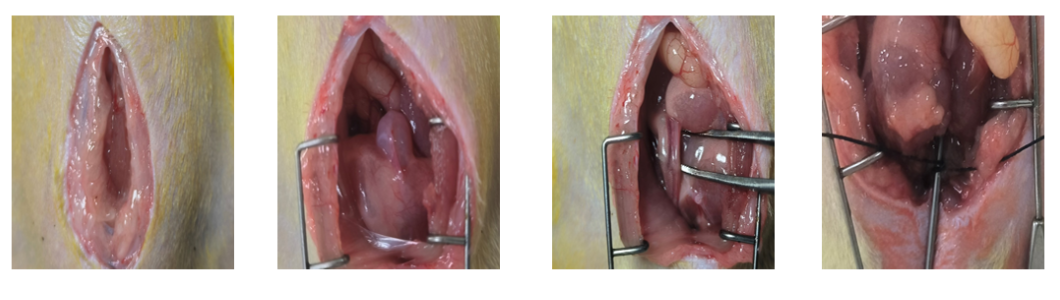

过程展示

2、在成功暴露出膀胱后,顺着膀胱向下寻找尿道。在此过程中,必须格外小心,以尽量减少对前列腺的潜在损伤,确保尿道能够被准确识别并准备进行后续操作。

3、继续沿着尿道向下寻找,直至触及一个大约1mm左右的硬物。此时,使用10ml注射器的针头,配合结扎线,将尿道与该针头紧密结扎在一起。结扎完成后,轻轻拔出10ml注射器的针头,这样就在尿道上形成了一个狭窄的模型。